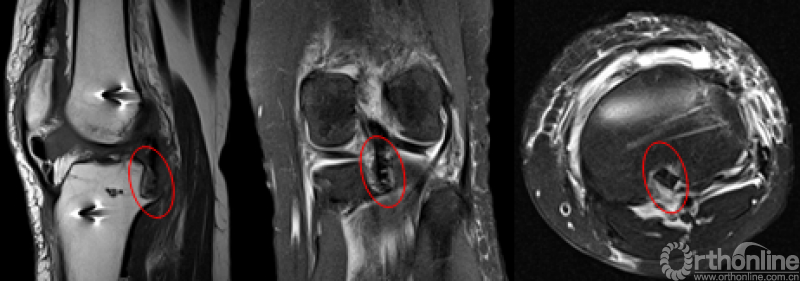

CT

MRI